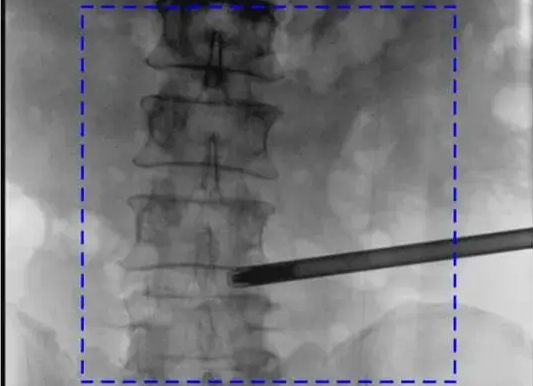

【CAOS2025骨科醫師年會】普愛醫療舉辦骨科手術機器人實操體驗活動

第十六屆中國醫師協會骨科醫師年會(CAOS 2025)于2025年6月19日-22日在湖南長沙舉行。普愛醫療攜骨科手術機器人與骨科影像解決方案亮相,同步開展設備實操體驗,邀請骨科手術機器人臨床應用專家演示指導,為參會者提...